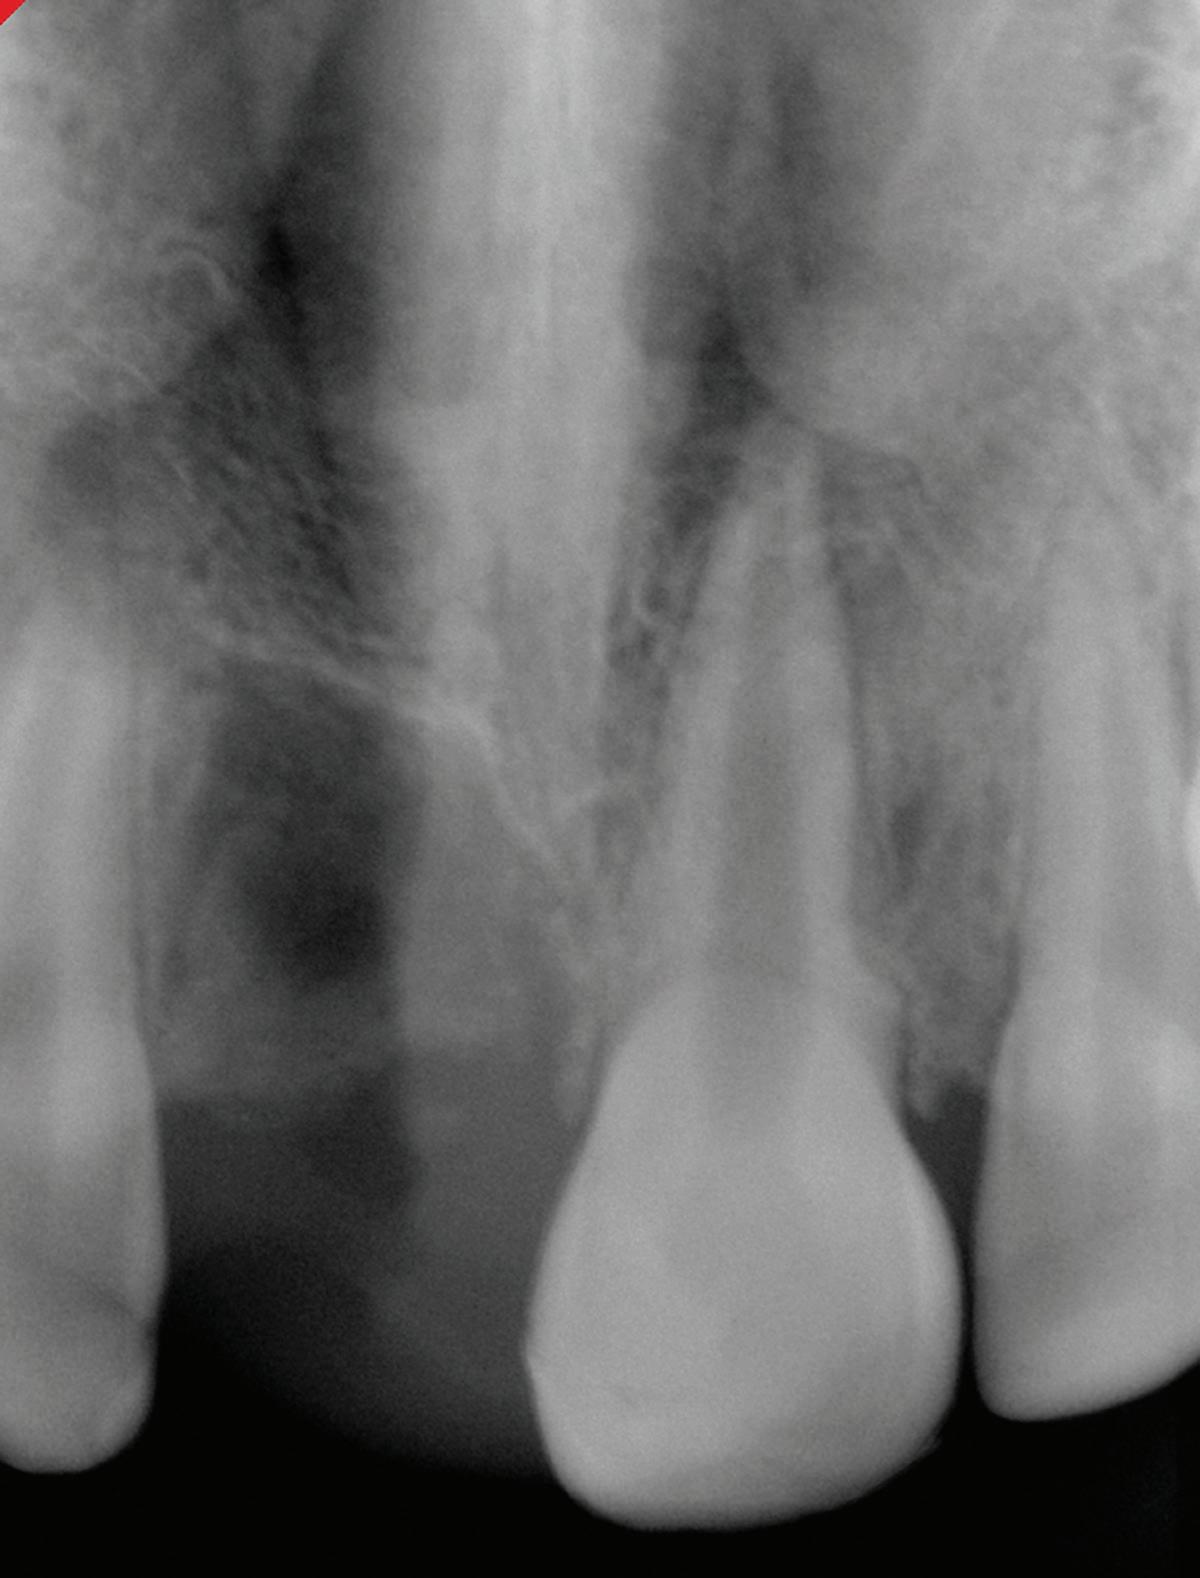

Fig 4. Fenestration involving the maxillary right first molar. A. The periapical radiograph fails to demonstrate the presence of a fenestration at the mesiobuccal root. B. The axial CBCT image clearly depicts the fenestration. C. The coronal CBCT image also reveals the fenestration.

It also could be argued that the potential for iatrogenic complications, including extrusion-related nerve injuries or sinus involvement, supports a more universal application of preoperative CBCT, especially in posterior teeth or anatomically high-risk zones. For instance, bony fenestrations, which create direct communication between the root surface and soft tissue due to absence of cortical bone, are virtually invisible on standard 2D radiographs. These defects significantly increase the risk of overinstrumentation; endodontic irrigant and obturation material extrusion; and postoperative inflammation, particularly when the root apex lies adjacent to neurovascular structures or sinus cavities. CBCT is the only reliable tool to detect fenestrations preoperatively. It allows visualization of cortical bone thickness and can identify discontinuities in the buccal or lingual plate that predispose to soft tissue perforation (Fig 5).

In a CBCT-based study by Nalbantoğlu et al, fenestrations were identified in approximately 35.7% of maxillary anterior teeth, with the majority occurring in the apical third of the root. 28 Dehiscence was observed in 20% of teeth, and a significant proportion of cases were associated with thin buccal bone, particularly in patients with periodontal biotypes exhibiting bone thickness of 1 mm or less. These findings highlight the vulnerability of anterior teeth, especially in individuals with thin cortical bone, to structural defects such as fenestrations.